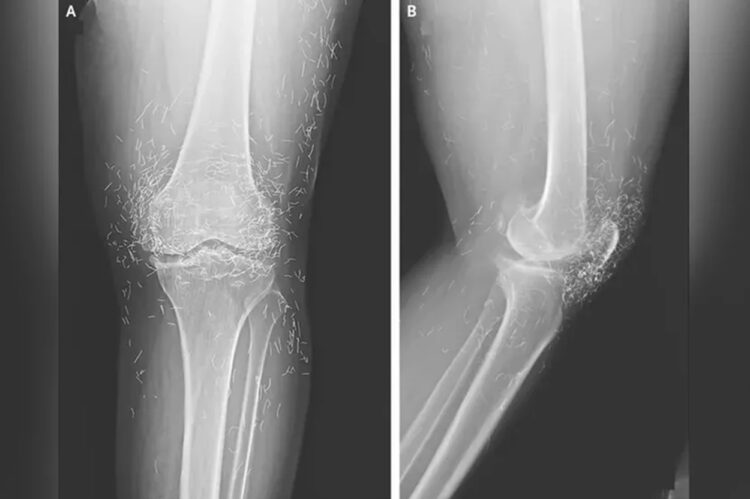

Situasi memburuk hingga akhirnya pasien harus kembali ke rumah sakit. Pemeriksaan rontgen mengungkapkan adanya penebalan dan pengerasan bagian dalam tulang tibia serta pertumbuhan tulang di lutut, gejala khas osteoarthritis.

Lebih mengejutkan, dokter menemukan ratusan benang emas kecil tertanam di jaringan di sekitar lutut.